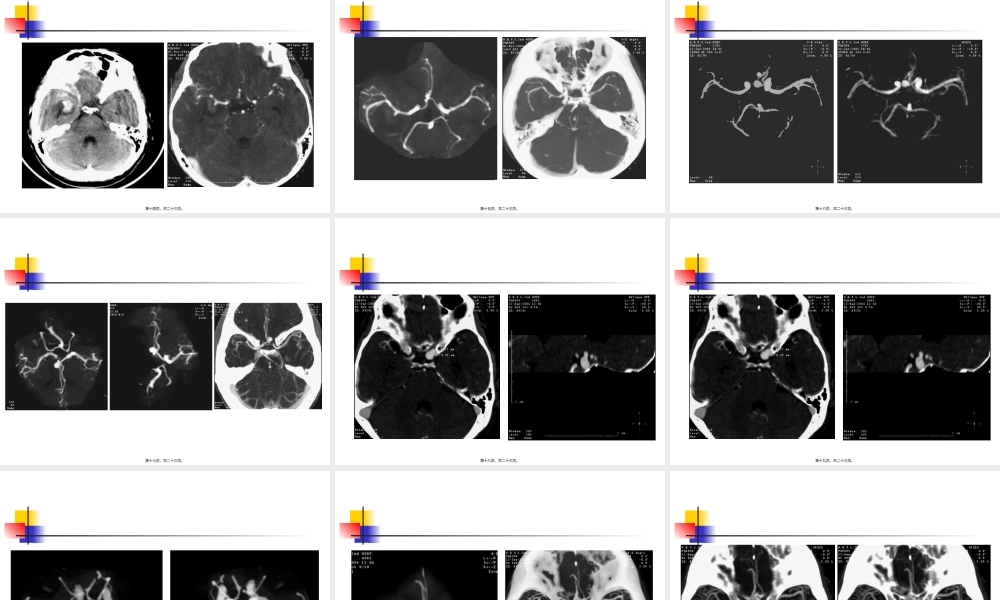

脑部CTA后处理第一页,共二十三页。一、脑的动脉(dòngmài)1、颈内动脉(dòngmài)系2、椎-基底动脉系3、大脑动脉环第二页,共二十三页。脑动脉(dòngmài)的两个系统来源颈内动脉(dòngmài)系端脑前2/3间脑的前部椎基底动脉系端脑后1/3间脑后部脑干、小脑第三页,共二十三页。颈内动脉系和椎-基底动脉系吻合形成封闭的七边形血管环。意义(yìyì)是一种代偿的潜在装置。缺血性脑血管疾病时,侧枝循环最充分的供血来源。第四页,共二十三页。1、扫描范围:后床突下30mm~后床突上60mm;造影剂(I)300mg/ml,100~140ml,3~4ml/s,12~25s后扫描,层厚1~2mm,Pitch1.0~1.5,120~140kV,120~250mA2、重建方法MIP、VR或SSD,显示颈内动脉虹吸部,Willis环,大脑(dànǎo)前、中、后动脉主干及其2~3级分支血管第五页,共二十三页。第六页,共二十三页。第七页,共二十三页。第八页,共二十三页。第九页,共二十三页。第十页,共二十三页。第十一页,共二十三页。第十二页,共二十三页。第十三页,共二十三页。第十四页,共二十三页。第十五页,共二十三页。第十六页,共二十三页。第十七页,共二十三页。第十八页,共二十三页。第十九页,共二十三页。第二十页,共二十三页。第二十一页,共二十三页。第二十二页,共二十三页。内容(nèiróng)总结脑部CTA后处理。大脑动脉环(Willis环)。颈内动脉系和椎-基底动脉系吻合形成(xíngchéng)封闭的七边形血管环。造影剂(I)300mg/ml,100~140ml,3~4ml/s,12~25s后扫描,层厚1~2mm,Pitch1.0~1.5,120~140kV,120~250mA。前交通支动脉瘤(MIP、VR、SSD)。CTA(左颈内动脉瘤)MIP第二十三页,共二十三页。